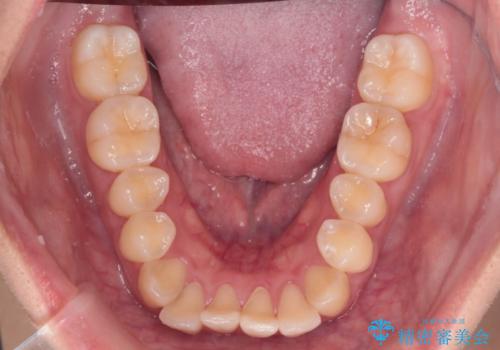

【インビザライン】反対咬合を治したい

- 前歯の反対咬合を主訴に来院されました。

インビザラインにて歯列弓の拡大により叢生の改善を行うことができ、患者様にも満足していただました。